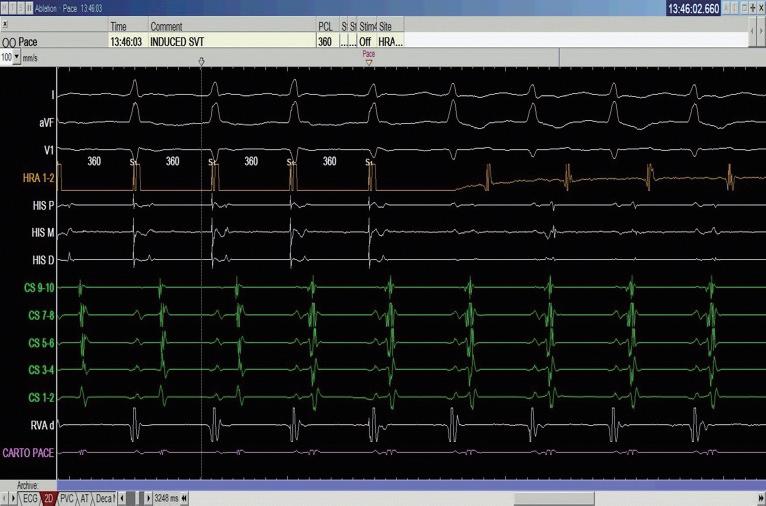

中華民國心律醫學會‧ Taiwan Heart Rhythm Soclety ‧中華民國 111 年 9 月出刊 我們在此報告一個來進行 PSVT 電燒的 55 歲 女性,沒有其他慢性病症,甲狀腺檢查正常,因為 PSVT 前往急診,發作時十二導程心電圖如下 ( 圖一 ) , 看起來是 short-RP 的 tachycardia 並且有 electrical alternans 的現象,第 12 個波組看起來比較不一樣,推測有可能 此時 tachycardia 有短暫的 termination 又被第 13 個波 組的 VPC 重新啟動一輪的 SVT 。 進入 EP lab ,在一開始進行 Ventricular extra stimulus test (VEST) 檢查時,心房訊號的傳導 是中軸傳導 (Concentric atrial activation pattern),而 且我們觀察不到明顯遞減傳導的現象 (Decremental conduction),一般而言正常經過房室結的傳導無論 順向或逆向多半會有 Decremental conduction 的情 況,這讓人懷疑隱藏在著一條在中軸的副傳導路徑 (Accessory pathway)( 圖二 ) 病人的心律不整很容易在右心房用 rapid pacing 誘 發,誘發時會看到心房心室傳導逐漸出現 Wenckebach 的現象,接下來就產生一個 Short-RP 的 tachycardia, 在 tachycardia 時的 atrial activation sequence 在 CS 導 程的表現看起來與我們先前在做 RV pacing 時是一致 的 ( 圖三 ) ( 圖二 ) ( 圖一 ) ( 圖三 ) 7NO.047

HIS refractory VPC 做確認時(圖五),結果又有點出乎 意外,當

中華民國心律醫學會‧ Taiwan Heart Rhythm Soclety ‧中華民國 111 年 9 月出刊 ( 圖四 ) ( 圖六 ) ( 圖五 ) ( 圖八 ) 我們接著進行 Para-hisian pacing 來證實我們的想 法,我們將原本放在 HRA 的電極放到在 Para-hisian 的 V site,邊做 pacing 邊調降 pacing voltage,一路將 voltage 降到 0.3mV 都可以 capture myocardial 並傳回 atrium 去,其中的 V-A interval 都保持一致,證實這個 accessory pathway 的存在(圖六)。 由於看起來是不管在 RV pacing 或心律不整跳起 來時 Atrial activation 都以 CS 9-10 最早,儘管 CS lead 在 fluoroscopy 的 LAO view 下放得比較深,我們先 在 Tricuspid ring 的 septal site 靠近 CS9-10 的地方進行 電燒。( 圖七 ) 我們在右側電燒時,不管是電燒或者 mechanical bump 的方式,都可以將正在跳的心律不整 終止。這時候心律不整下的 V-A 訊號看起來也比之前 寬,然而類似的心律不整依舊會被誘發。 我們於是考慮這條 accessory pathway 其實比較 broad band,並且牽扯到 LV 的 septum,最終我們成 功在 Mitral subvalvular 的 septal site 將這條 accessory pathway 燒掉,並且達到 complete VA block(圖八), 最終電燒位置即在先前右側電燒點的對面(圖九, 圖中 CS catheter 有外拉,電燒導管位置近似於圖七 CS 9-10)。 這時候為了區分 AVNRT 與使用 septal kent 作 為傳導的 orthodromic AVRT,或者有一個很長 PR interval 的 AT( 儘管在前面的誘發過程較為不像 ),我 們使用 RV 的導管做 overdrive pacing 來 entrain 這個 tachycardia。 在成功 RV entrainment 停止後,我們觀察 tachycardia 傳導回來的方式是 V-A-V response ,這 個反應排除了心房頻脈。接著我們計算 PPI-TCL 以 及 Stimulus-atrial interval minus ventriculoatrial interval (SA-VA),可以看到 PPI-TCL 數值為 114ms, 而 SA-VA 為 68ms。(圖四)PPI-TCL 剛好在一個邊 界值,是嗎?這裡有個小陷阱,我們應該要對 delta A-H 做校正,在本圖中因為 His 的訊號不明顯,所以我們 使用 delta A-V 做校正(假設 HV 為定值不太會變), 可以看到 PPI 的 A-V 因為 decremental properties 的 關係較長(280ms),而平常 tachycardia 在跳的時候 A-V interval 較短(194ms),校正後的 corrected PPITCL 其實是 114-(280-194)= 28ms。 從這樣的檢查代表應該是 septal accessory pathway 造成的 orthodromic AVRT,然而當我們進一步做